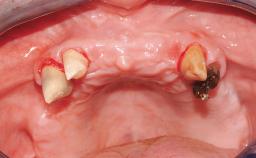

A 31-year-old man presented to our clinic 30 days after a motor vehicle accident in which he had suffered a dentoalveolar fracture in the anterior maxilla, including avulsion of teeth 12 and 11 and luxation of tooth 21. He was first treated on the night of the accident in a small city hospital with no oral and maxillofacial surgeon on the staff. A wired retention had been applied and the teeth repositioned to the best of the clinicians’ abilities. When he first presented to our care, the patient showed extrusion of teeth 12 and 11 associated with gingival recession due to bone loss in the anterior maxilla, and the stainless steel wires were still present.